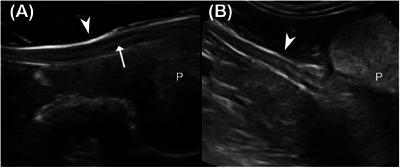

In veterinary medicine, deferent ducts are described as being visible on ultrasound only when pathologically enlarged. Abnormal ultrasonographic enlargement of the deferent ducts has primarily been described secondary to infectious and neoplastic diseases; however, no studies have evaluated the normal ultrasonographic features of these structures. This prospective observational study aimed to describe the ultrasonographic appearance of deferent ducts and assess ultrasound reliability in their identification in intact and neutered dogs without genitourinary disease. The study aimed also to compare ultrasonographic measurements with postmortem anatomical ones and to investigate the relationship between duct identification, size, and intrinsic factors of the patient. The study consisted of ex vivo and in vivo phases in which ultrasonographic assessments of the ducts were conducted at the level of the prostate in longitudinal (location 1) and transverse (location 2) planes and the inguinal canal (location 3) and scrotal region (location 4) in longitudinal planes. A total of 80 deferent ducts were included. The ducts were visible as paired tubular hypoechoic structures delimited by two thin hyperechoic lines, with a target-like appearance on the transverse plane. The deferent ducts were identified in 97.5% of our population in at least one location, with locations 1 and 2 being the most reliable ones. Identification of the ducts was independent of reproductive status; however, reproductive status appeared to be the most significant factor influencing deferent duct size, with neutered dogs exhibiting smaller deferent ducts.

在兽医学中,只有在病理扩大时,输精管在超声检查下才可见。输精管异常的超声图像扩大主要继发于感染性和肿瘤性疾病;然而,尚无研究评估这些结构的正常超声特征。这项前瞻性观察性研究旨在描述输精管的超声表现,并评估在无泌尿生殖系统疾病的未绝育和已绝育犬中超声识别输精管的可靠性。该研究还旨在将超声测量结果与尸检解剖测量结果进行比较,并研究输精管识别、大小与患犬内在因素之间的关系。该研究包括体外和体内两个阶段,在纵向平面(位置1)和横向平面(位置2)的前列腺水平以及纵向平面的腹股沟管(位置3)和阴囊区域(位置4)对输精管进行超声评估。总共纳入了80条输精管。这些输精管表现为成对的管状低回声结构,由两条细的高回声线界定,在横断面上呈靶样外观。在我们的研究对象中,97.5%的犬至少在一个位置可识别出输精管,其中位置1和2是最可靠的识别位置。输精管的识别与生殖状态无关;然而,生殖状态似乎是影响输精管大小的最重要因素,已绝育犬的输精管较小。